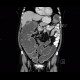

The most prominent finding in this examination was massive dilation of the colon with air-fluid levels indicating bowel obstruction (ileus). Its cause can be tracked down to sigmoid, where a tumorous thickening of the wall with extension into the mesosigmoid and involvement of local lymph nodes can be found. Small bowel loops remain relatively undistended thanks to competence of the ileocecal valve.